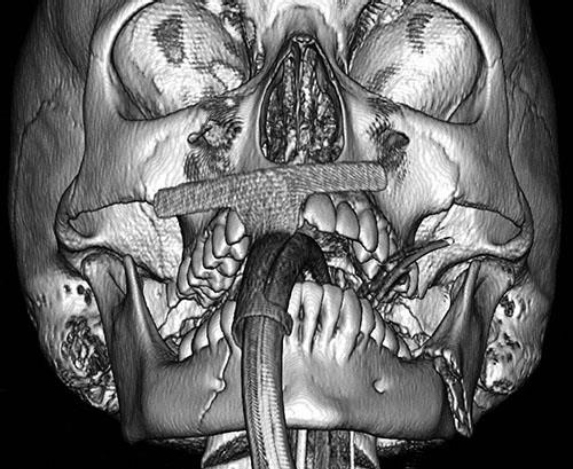

A 16-year-old girl is brought to the emergency department after sustaining fractures to the mandible in a rollover motor vehicle collision. She is intubated during the primary survey because of her critical airway. A CT scan is shown. Which of the following is the most appropriate treatment of this fracture pattern?

The correct response is Option C.

This CT scan shows right–body and left–angle fractures, both with clinically significant displacement. Modern facial fracture management dictates early primary reduction and repair; therefore observation and soft diet without surgery is incorrect, as is avoiding disturbance of the mandible and allowing 6 weeks of bone healing. Since she has reached the age of skeletal maturity permanent titanium hardware is an accepted modality of treatment; therefore it is incorrect to avoid hardware and rely on non-reduced maxillomandibular fixation. In addition, an angle fracture cannot typically be treated with maxillomandibular fixation alone, but requires a Champy plate or more rigid fixation. Open reduction and internal fixation of the right–body fracture, without repairing the left angle is incorrect, as Champy lines do not preclude the need for fixation. Open reduction and internal fixation of both the right body and the left angle fractures is correct, as both fractures need to be reduced, and then fixated, for the best chance of restoring occlusion.